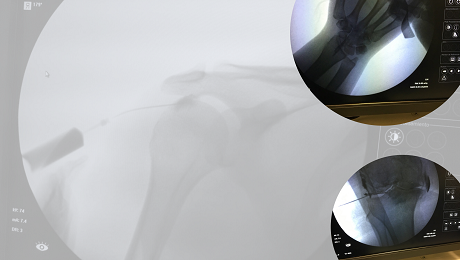

Manejo Intervencionista del Dolor

Una de nuestras mejores terapias es la aplicación de Técnicas Analgésicas Invasivas No Quirúrgicas, es decir, el MANEJO INTERVENCIONISTA DEL DOLOR, con lo que se trata de llegar directamente a los sitios que originan el dolor para infiltrar con medicamentos o estímulos con radiofrecuencia la zona dolorosa, consiguiendo así un alivio inmediato del dolor. que dependiendo de la enfermedad puede ser temporal o definitivo

Infiltración articulaciones

Consiste en la inyección de medicamentos directo en la articulación afectada con el fin de disminuir el dolor y regresar la movilidad. Procedimiento que se realiza con seguridad en dolorclinic guiado por ultrasonido o rayos x, prácticamente indoloro y con resultados a corto y mediano plazo muy importantes